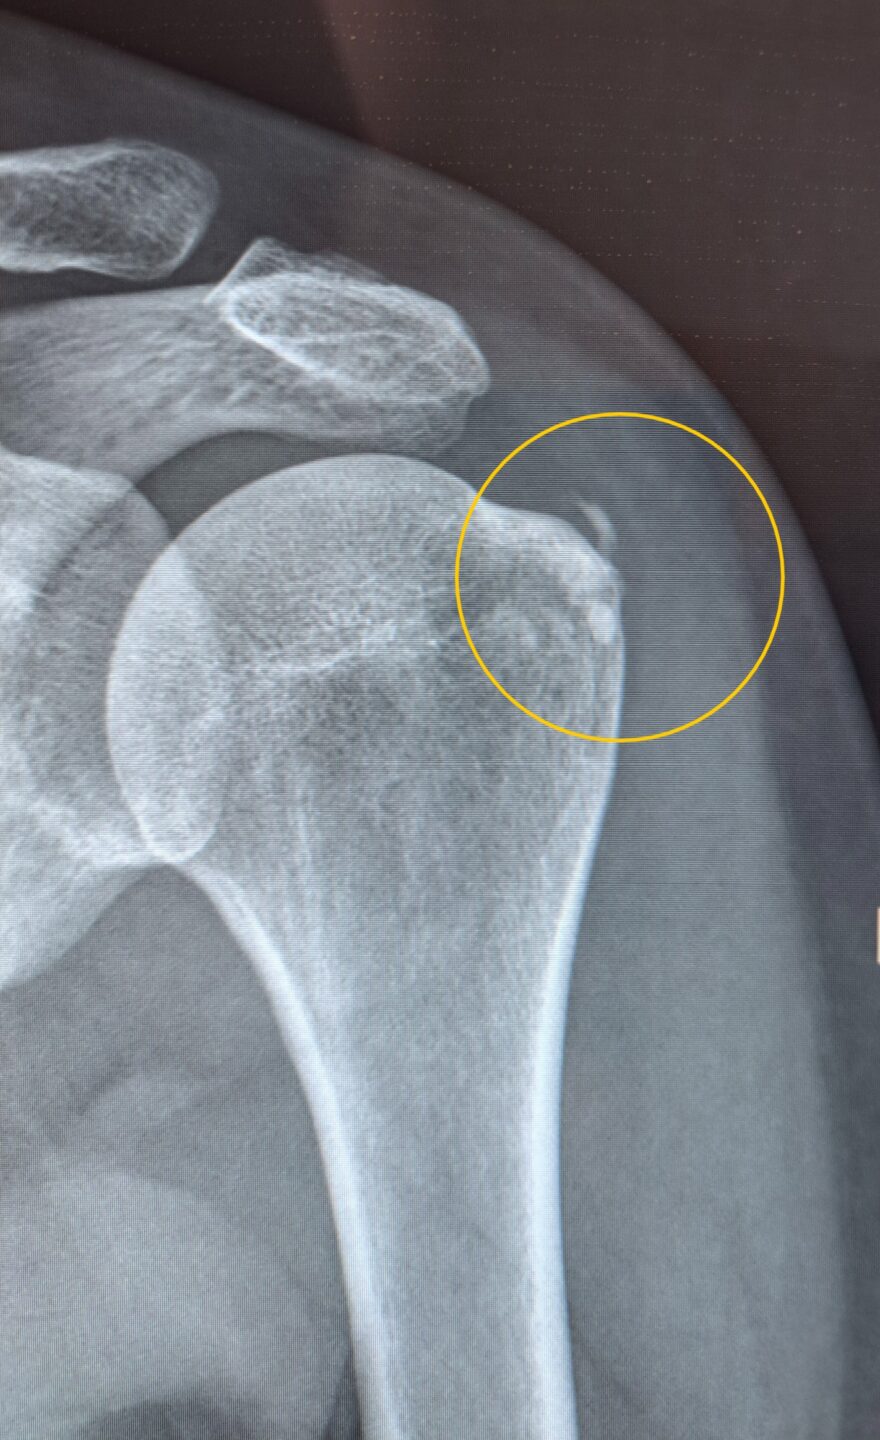

V fizioterapevtsko ambulanto meridian-fit prihaja 44 let stara gospa z bolečino in omejeno gibljivostjo v desni rami. Opravljen je bil tudi RTG slikovno diagnostiko kjer nakazuje na kalcinacijo desne rame. Glede na teste, ki smo jih izvedli v ambulanti in na podlagi slikovne diagnostike smo lažje sestavili plan zdravljenja za našo pacientko.

Po 12 terapiji v meridian-fit je gospa opravila RTG, kateri je pokazal na uspešno zdravljenje kalcinacije v rami. Ob zadnji fizioterapevstki obravi smo izvedli tudi funkcionalno testitanje kjer gospa ni več čutila bolečine.

Po začetnih šestih terapijah je bila funkcionalnost rame izrazito izboljšana. Gibljivost se je približala normalnim vrednostim na primerjavi z nepoškodovano ramo, bolečina pa se je zmanjšala, v mirovanju je skoraj popolnoma izginila. Ob dvigovanju roke se je ohranil le še blag nelagodje. Po devetih terapijah je pacientka začela samostojno izvajati vaje, bolečina ob vsakodnevnih aktivnostih se je znatno zmanjšala, pri določenih gibih, kjer je roka dvignjena nad nivojem glave, je občutila le še rahlo špikanje, ki ni vplivalo na njeno funkcionalnost. Po dvanajstih terapijah je RTG potrdil uspešno zdravljenje kalcinacije, medtem ko je funkcionalno testiranje pokazalo popolno odpravo bolečine. Pacientka je dosegla pomembno izboljšanje kakovosti življenja, saj je lahko normalno izvajala vse dnevne aktivnosti brez omejitev ali bolečin.